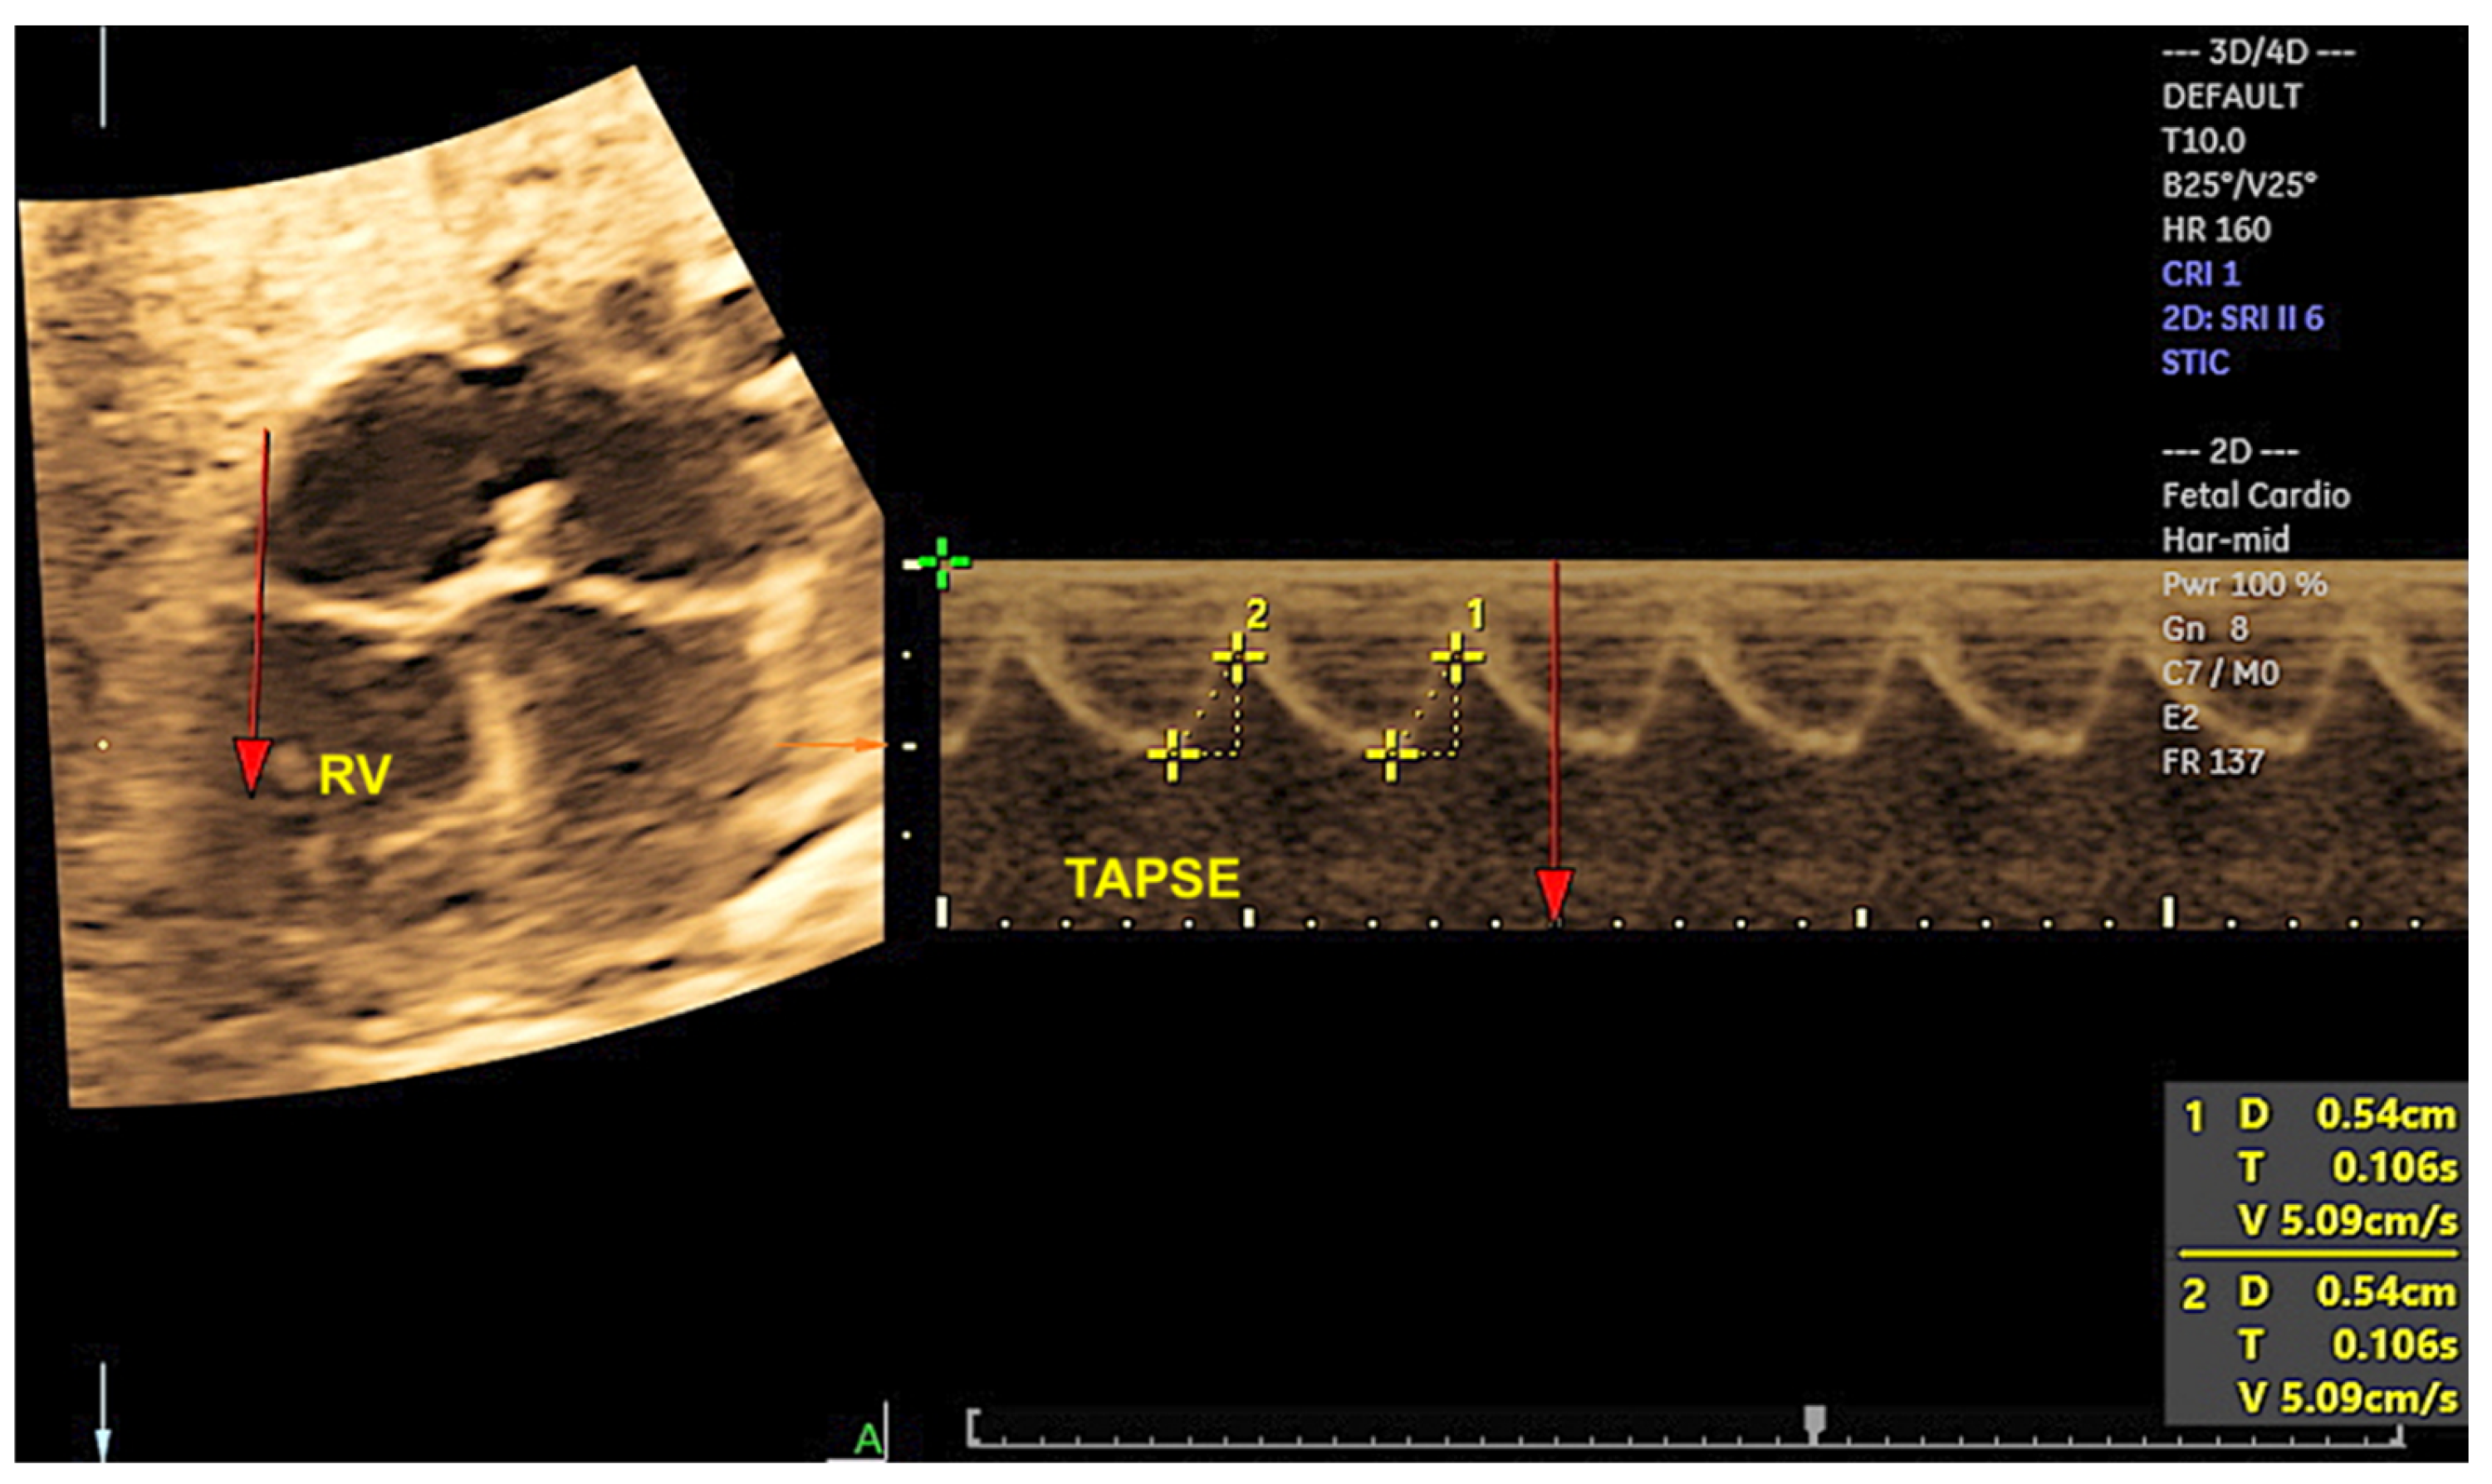

- Tanis JC, Mohammed N, Bennasar M, Martinez JM, Bijnens B, Crispi F; et al. Online versus offline spatiotemporal image correlation (STIC) M-mode for the evaluation of cardiac longitudinal annular displacement in fetal growth restriction. J Matern Fetal Neonatal Med. 2018 Jul;31(14):1845-1850.